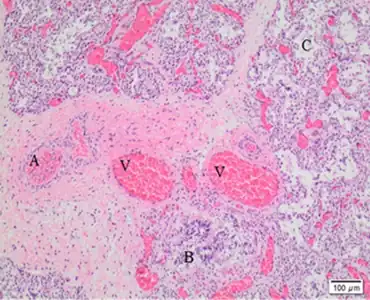

| Dilated capillaries are not in contact with alveolar epithelium | |

Most cases of ACD are caused by mutations affecting the gene FOXF1 or its nearby enhancer region.[3] Exactly how these mutations lead to abnormal lung development is unknown. Abnormal lung development is characterized by thickened alveolar interstitium, misplacement of pulmonary capillaries away from the alveolar surface, and fewer capillaries overall. This results in poor gas exchange and pulmonary hypertension.[1] There is evidence for connections between pulmonary arteries and systemic vessels, which would additionally contribute to poor blood oxygenation.[4]

How mutations affecting FOXF1 or its regulatory region cause ACD is unknown. ACD-causing mutations result in abnormal development of lung vasculature and alveoli. In ACD, the interstitium of alveoli is thickened, with few to no capillaries located at the alveolar surface to perform gas exchange, and with lower capillary density overall. This reduction in capillaries and their misplacement away from the alveolar surface result in poor oxygenation and retention of carbon dioxide in the blood and high pulmonary blood pressure.[1] There is also evidence of direct connections between pulmonary arteries and systemic vessels, which would deliver deoxygenated blood to the body, also contributing to low blood oxygenation.[4]

Another characteristic histologic finding is the presence of a pulmonary vein located next to a pulmonary artery and bronchus in the same bronchovascular bundle. In a normal lung, the pulmonary vein courses with lymphatic vessels in the lung septa.

The gold standard for ACD diagnosis is by examination of lung tissue under a microscope. The diagnosis is made if the pathologist sees the characteristic findings of ACD: misplaced pulmonary veins adjacent to pulmonary arteries, abnormal alveoli with thickened interstitia and abnormal capillary development. Due to the rapidly progressive course of ACD, this diagnosis is frequently made during autopsy. If ACD is suspected early, examination of tissue from lung biopsy results in the quickest diagnosis.[1] Genetic testing for FOXF1 is now available and can allow for slower but non-invasive diagnosis. As not all disease-causing mutations are known, false negatives or results of uncertain significance are possible with genetic testing.[2]